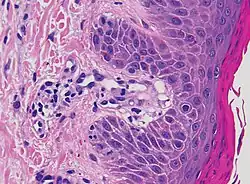

Additional testing may aid diagnosis. A skin biopsy may be taken to determine capillaritis of dermal vessels.[8] Capillaritis or pigmented purpura is skin condition that has brown-reddish patches on the skin, which is caused by leaky capillaries.[9] Such skin biopsies are sent to a laboratory for a pathological examination, where each biopsy is observed under a microscope.[3] A dermatologist may also perform a dermatoscopy.[3]